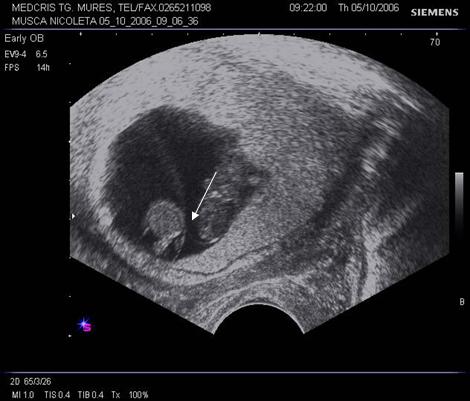

Fig nr 37. Aceeasi sarcina gemelara de 6 sapt., sectiune fara embrioni,cu sacii amniotici caracteristic dispusi in ochi de bufnita